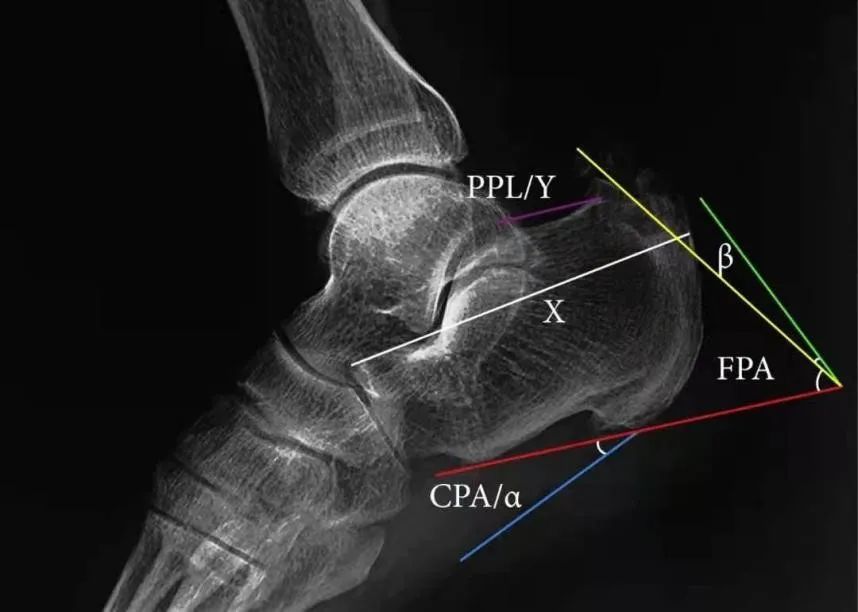

X:Fowler and Philips angle,44°-69°

CLA角:Chauveaux-Liet  Angle,CLA=α-β,>12°怀疑,X/Y值:<2.5高度怀疑

FPA和PPL不可靠,Haglund综合征与跟腱钙化和跟骨后方骨刺关系密切。